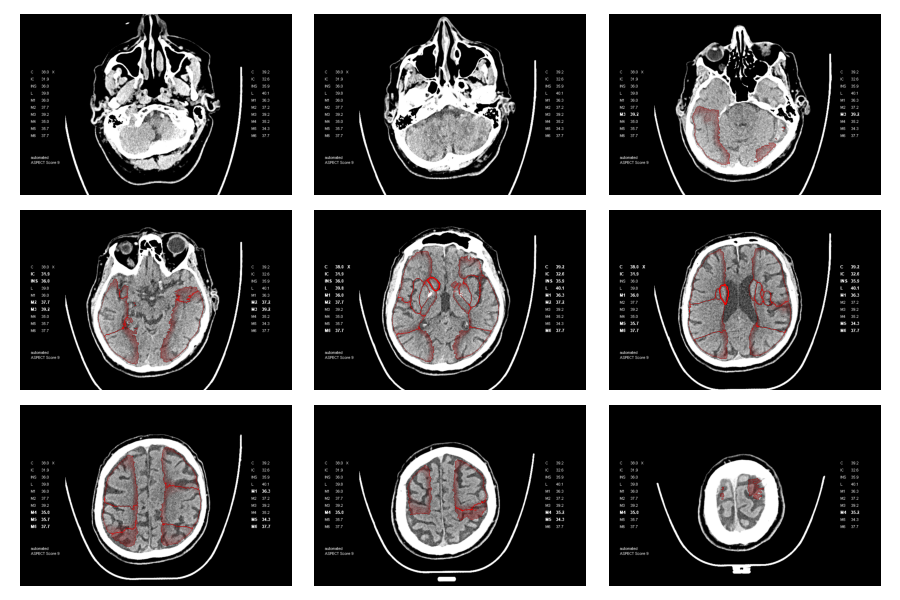

The baseline established by the existing point-cloud overlays was instrumental for deriving segmentation masks. However, initial methods employing morphological operations coupled with connected component analysis did not yield robust segmentation masks from the point cloud data. The primary difficulty stemmed from the fact that many current overlays exhibited substantial gaps or were entirely devoid of sections of the region outlines, as depicted below, where gaps and noisy borders are clearly visible. Although it was feasible to develop morphological operations tailored to function on certain overlays, a universally reliable and effective implementation of this technique proved unattainable.

Below, the predicted ASPECTS regions of a validation sample on a single slice and the entire predicted volume is visualized.